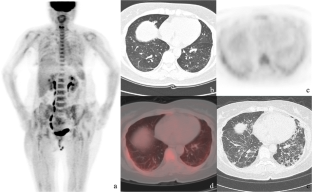

This study aimed to investigate the multiple values of 18F-FDG PET/CT in detecting malignant tumors, evaluating myopathy, and determining interstitial lung disease in patients with idiopathic inflammatory myopathy (IIM). We retrospectively analyzed the data of 38 patients who were examined by 18F-FDG PET/CT and eventually diagnosed as IIM. We also collected the data of another 22 cases with negative PET/CT as the control. Pulmonary HRCT images were acquired simultaneously with regular 18F-FDG PET/CT imaging for each patient. Image analysis included the presence of malignant lesions, muscular FDG uptake, and interstitial lung disease and its imaging features. IIM was classified into polymyositis (PM), classic dermatomyositis (CDM), and clinical amyopathic dermatomyositis (CADM). All suspected malignant lesions were confirmed by histopathological examination. Interstitial lung disease was diagnosed by HRCT. Rapidly progressive interstitial lung disease (RP-ILD) was determined according to clinical follow-ups. The significance of 18F-FDG PET/CT in the detection of malignancy, observation of activity of myopathy, and determination of interstitial lung disease in IIM patients was explored based on the final clinical diagnosis. In the 38 patients with IIM, 3 cases were classified as PM, 18 as CDM, and 17 as CADM. PET/CT correctly detected 7 cases (18.4%) of malignant tumors, and all of which were found in CDM and PM patients. The muscular FDG uptake in IIM patients was higher than the control population, and it was higher in patients with myopathy (including PM and CDM) than in patients with CADM. The muscular FDG uptake in IIM patients was correlated with elevated serum creatine kinase level (r = 0.332, P = 0.042) and impaired muscle strength (r = −0.605, P < 0.001). Interstitial lung disease was detected by HRCT in 30 patients (78.9%), and 7 of them were eventually confirmed as RP-ILD, according to the clinical outcome. The FDG uptake in lung lesions of RP-ILD patients was higher than those with chronic interstitial lung diseases, even though no significant difference was found between the CT features of RP-ILD and chronic interstitial lung disease. When SUVmax ≥ 2.4 was employed as the threshold for RP-ILD prediction, the diagnostic efficiency was yield with a sensitivity of 100.0% (7/7), specificity of 87.0% (20/23), and accuracy of 90.0% (27/30), respectively. For IIM patients, 18F-FDG PET/CT has multiple values in identifying malignancies, observing the status of inflammatory myopathy, detecting interstitial lung disease, and predicting the occurrence of RP-ILD. Therefore, it is recommended to use PET/CT in the clinical course of diagnosis and management of IIM.